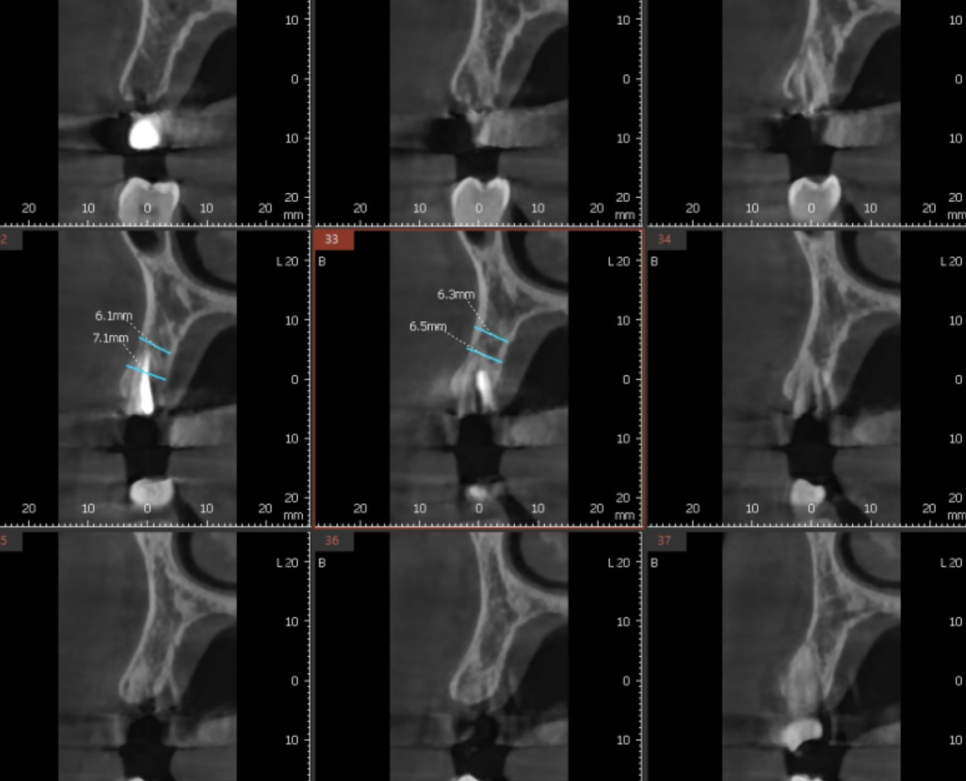

1개를 심는 간단한 임플란트도

ct 촬영을 진행하여

내부 뼈 상태를 확인합니다.

다행히 뼈는 충분하여

잇몸 안에 묻어두지 않고 작은 나사를 연결하고 마무리지었습니다.

이럴 경우 골 유착만 잘되면

임플란트 완성 기간이 짧아진다는 장점이 있죠.

240704 쇠 기둥 아래 임플란트가 숨어져있습니다 .